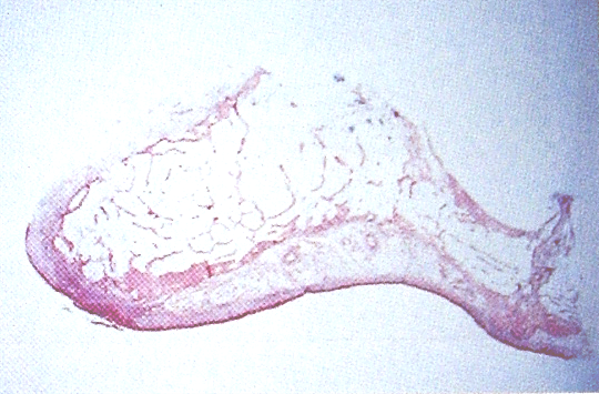

矢状面组织切片图

10.颤动线(vibrating line)

位于软腭与硬腭的交界部位。发“啊”音时软腭升高,发音结束后又复归原位,故又称“啊”线。

堵住鼻孔用鼻子出气会使软腭向下降,能明确观察到颤动线。

该线通常作为决定义齿基托后缘的标志,分前、后颤动线,两者之间为后堤区,宽约2~12mm 。